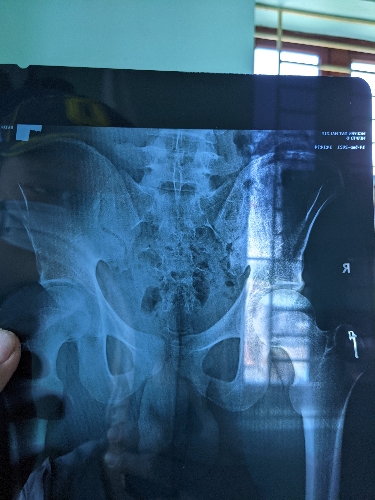

Chào bác sĩ, mấy hôm nay em có cảm giác tê ở vùng bìu tinh hoàn không đau, thi thoảng có cảm giác nhói vài lần rồi hết, khi em đi lại thì ko thấy cảm giác, chỉ khi ngồi em còn có cảm giác nhói ở phần xương mông ạ, cách đây nửa tháng em có đi khám ở pk nam khoa, kết quả siêu âm ,xét nhiệm của em đều ko có vấn đề gì, bác sĩ tư vấn tình trạng giúp em với ạ...em cảm ơn!